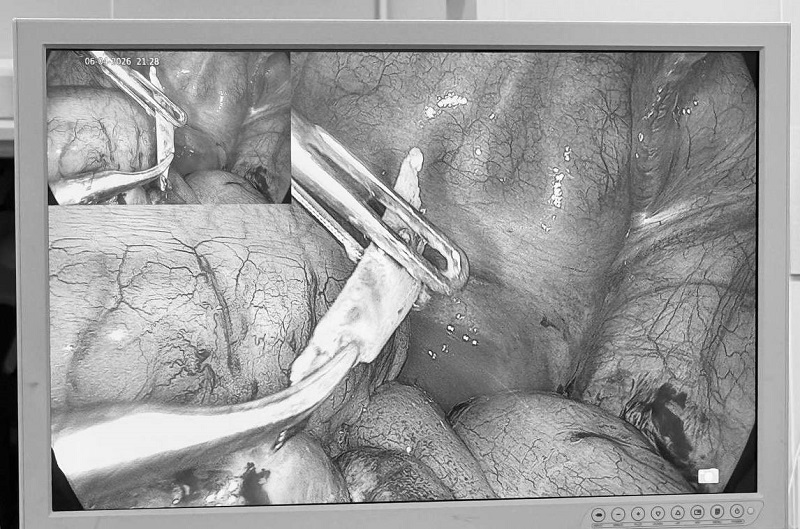

Dị vật đâm thủng ruột, nam thanh niên được phẫu thuật cấp...

Tưởng chừng chỉ là rối loạn tiêu hóa thông thường, nam thanh niên đến Bệnh viện Đa khoa MEDLATEC thăm khám thì phát hiện đâm thủng ruột non, tiềm ẩn nguy cơ...